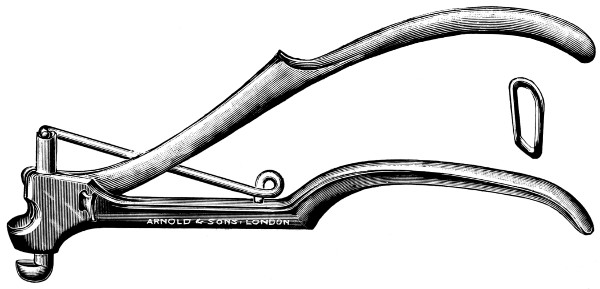

Fig. 6. Cushing’s Clips. A, The holder of the clips; B, A clip ready to be applied; C, Two clips applied to the middle meningeal artery.

Hæmorrhage from the middle meningeal artery may be controlled by ligature or torsion, and added to these methods we have one other, recently introduced by Cushing—silver wire ‘clips’. These clips[19] are U-shaped, loaded on a magazine, picked up as required in the jaws of a specially indented forceps, and clipped on to the vessel—usually one on either side of the bleeding-point.